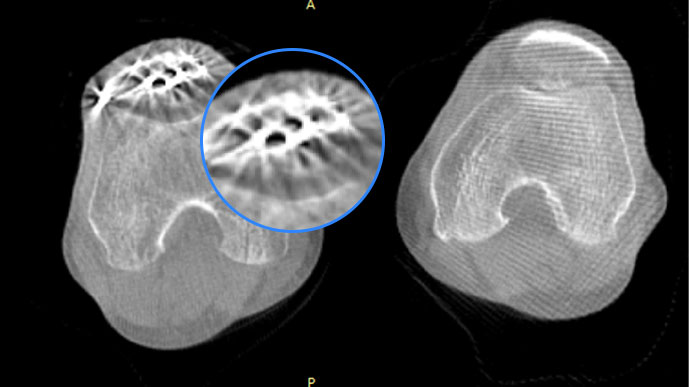

智能金屬偽影抑制算法

關閉金屬偽影校正

開啟金屬偽影校正